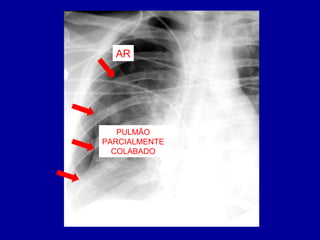

• PNEUMOTÓRAX >>> ACÚMULO DE AR

PNEUMOTÓRAX

PULMÃOP

AR

PULMÃO

PARCIALMENTE

COLABADO